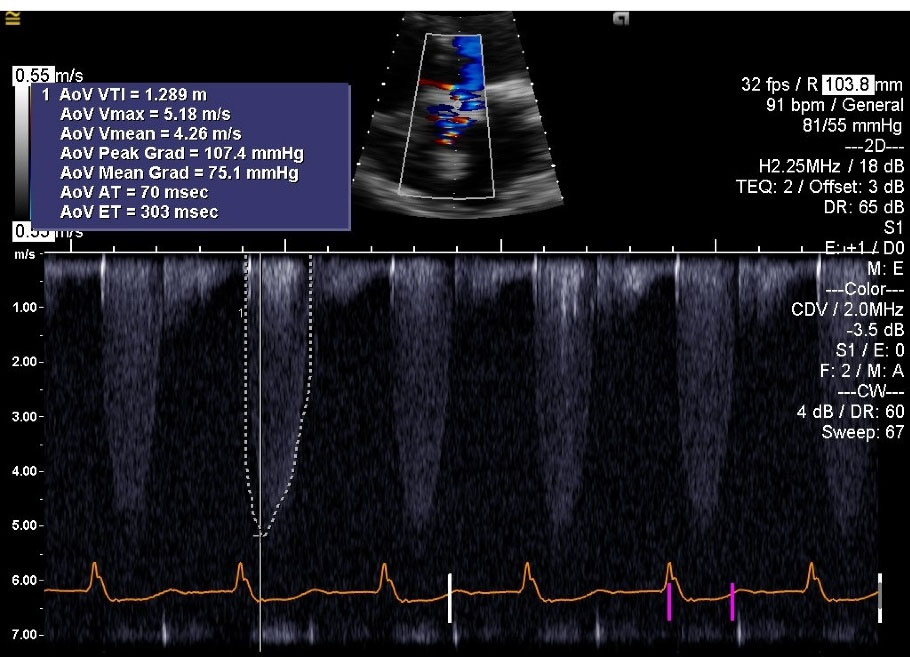

A 65-year-old male patient with past medical history significant for coronary artery disease (CAD), and aortic valve stenosis. He underwent coronary artery bypass graft (CABG) surgery, and aortic valve replacement with a Saint Jude Epic # 27 bio-prosthesis, 11 years prior to admission. He had severe oxygen dependent COPD, chronic kidney disease stage IV, renal cell carcinoma, and history of GI bleed. He was admitted to the hospital with progressive severe dyspnea, and hypotension. At presentation, the patient’s blood oxygen saturation was 85-87% on supplemental oxygen, blood pressure of 70/50 mm Hg, and signs suggestive of fluid overload. Chest X ray revealed pulmonary congestion with bilateral pleural effusion. Laboratory tests showed an elevated serum BNP of 5600 pg/mL (Normal value = 0-80 pg/mL). Electrocardiogram (EKG) was suggestive of sinus rhythm with right bundle branch block (RBBB) and right axis deviation. Echocardiogram () revealed severe stenosis of the bio-prosthetic AV with a peak gradient of 107.4 mm Hg, mean gradient of 75.1 mm Hg, peak velocity of 5.18 m/s, AV area of 0.62 cm2, and preserved left ventricular ejection fraction (LVEF) of 60%. As the patient was in cardiogenic shock, he required vasopressors, including, norepinephrine, phenylephrine, and vasopressin. For respiratory support, he required Bi-level positive airway pressure (BiPAP). Continuous veno-venous hemodialysis (CVVHD) was utilized to treat acute worsening of chronic kidney disease and fluid overload.

jcvtr-14-197-g001

Figure 1. Pre-TAVR ViV echocardiogram; Color Doppler M-mode. Patient has 27 mm St. Jude bio-prosthetic aortic valve. AV peak gradient (AoV Peak Grad) is 107.4 mm Hg, AV mean gradient (AoV Mean Grad) is 75.1 mm Hg and peak velocity (AoV Vmax) is 5.18 m/s AoV, Aortic Valve